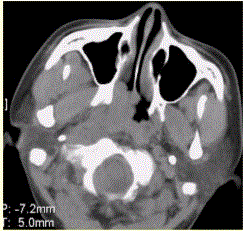

问题 患者男,45岁,鼻塞、涕中带血2周。查体颈部淋巴结增大。专科检查发现,鼻咽腔黏膜肿胀,左侧咽隐窝消失。CT表现如下图。 为明确病变范围和病期,下一步应选择的影像学检查为

选项 A.X线平片 B.CT C.MRI D.DSA E.鼻咽活检 F.鼻咽录像

答案 C